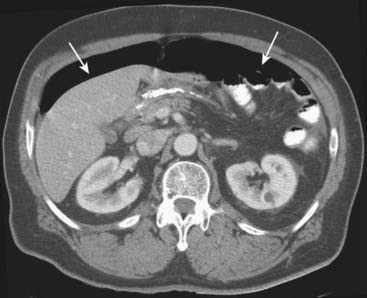

image

Figure 18-11 Free air from bowel perforation.

With the patient lying supine for this CT scan, free intraperitoneal air (solid white arrows) rises to the highest part of the abdomen beneath the anterior abdominal wall. Most cases of free intraperitoneal air (pneumoperitoneum) are due to perforations from gastric and duodenal ulcers.